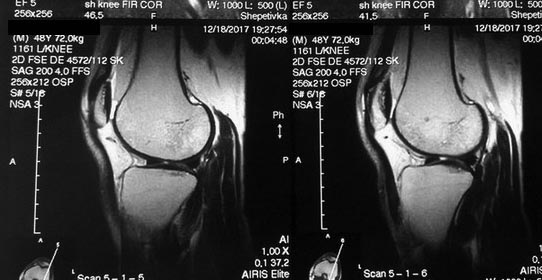

[Ortho] Остеомиелит надколенника

фото

Имя     : 13.jpg

Тип     : image/jpeg

Размер  : 67361 байтов

Url     : http://weborto.net:8080/pipermail/ortho/attachments/20171230/997926fb/attachment-0005.jpg